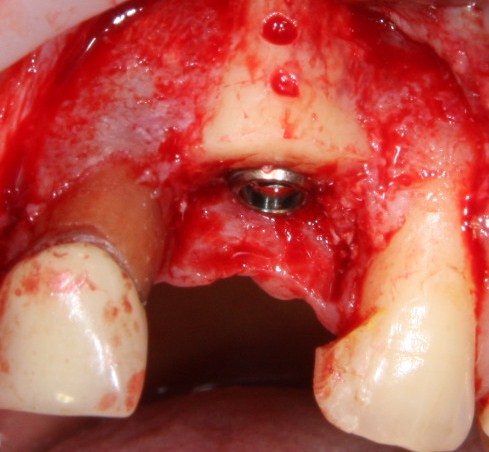

Делаем разрез, скелетируем костную ткань:

Как видите, коллагеновая мембрана полностью резорбировалась, а костный блок прижился и интегрировался на челюстной кости. Можно убрать винты:

и приступить к подготовке лунки под имплантат:

По существующим правилам, при установке импланта в области фронтальной группы зубов, его ось должна выходить на небную поверхность коронки или режущий край. Чего мы и добиваемся, контролируя процесс с помощью пинов.